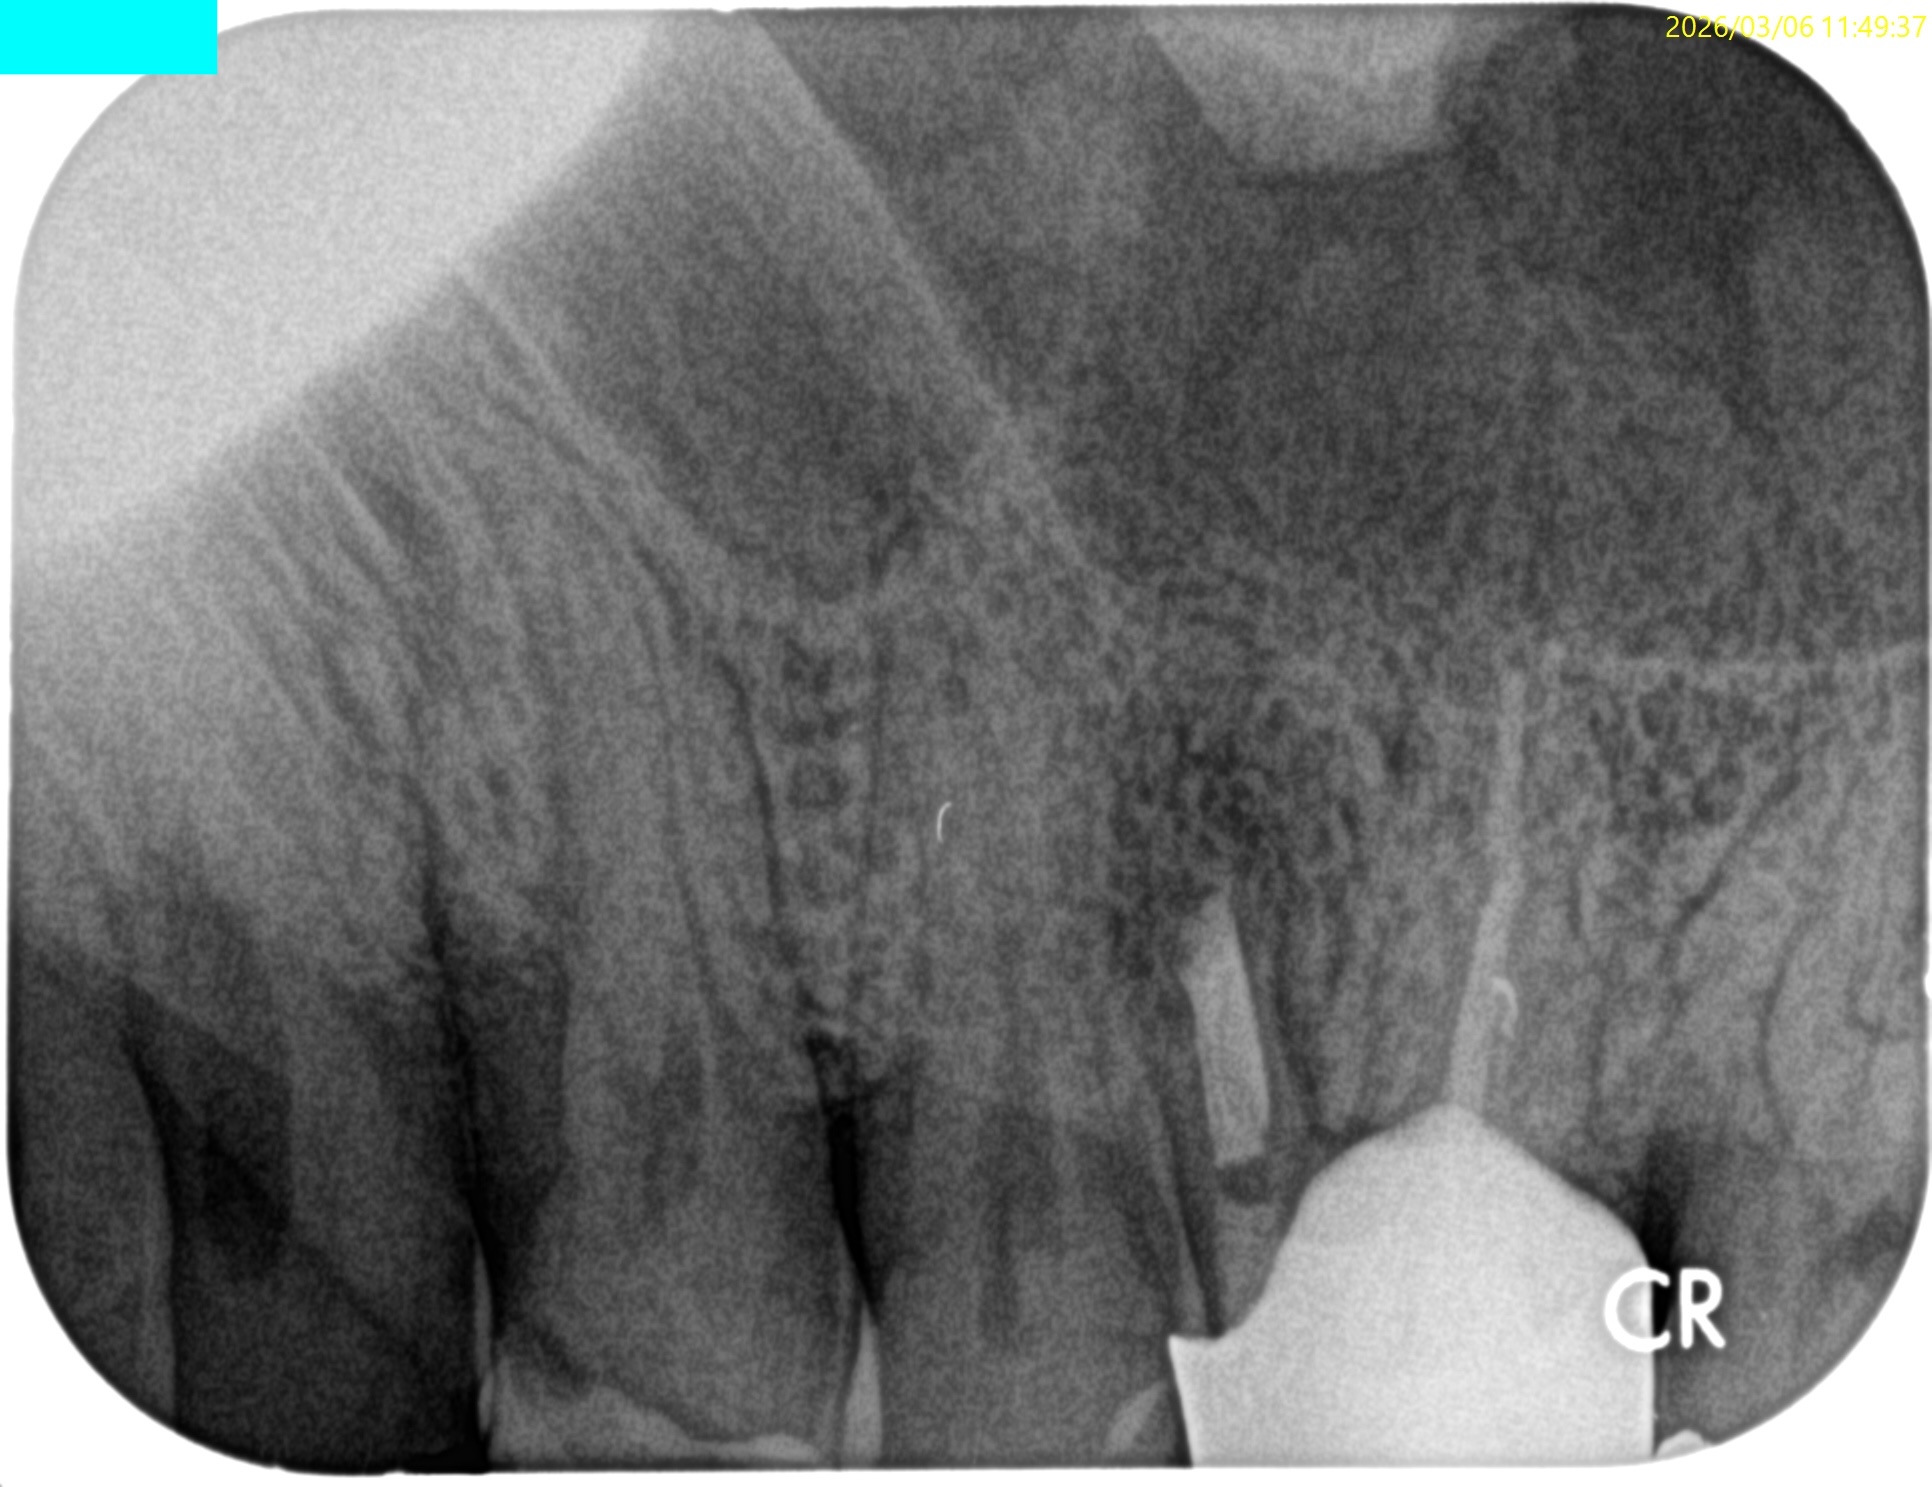

歯軸と並行になるようにCBCTのバーを動かした。

すると…

このような絵になる。

ここを、

こうすべきだろうか?

それともこのままで

いいだろうか?

私の頭に思い浮かんだの以下のケースだ。

のように逆根管充填しても治癒するだろうが、

中心に対して左右非対称に近くなることから私は修正しない道を選択した。

つまり、

この状態でOKと判断したのである。